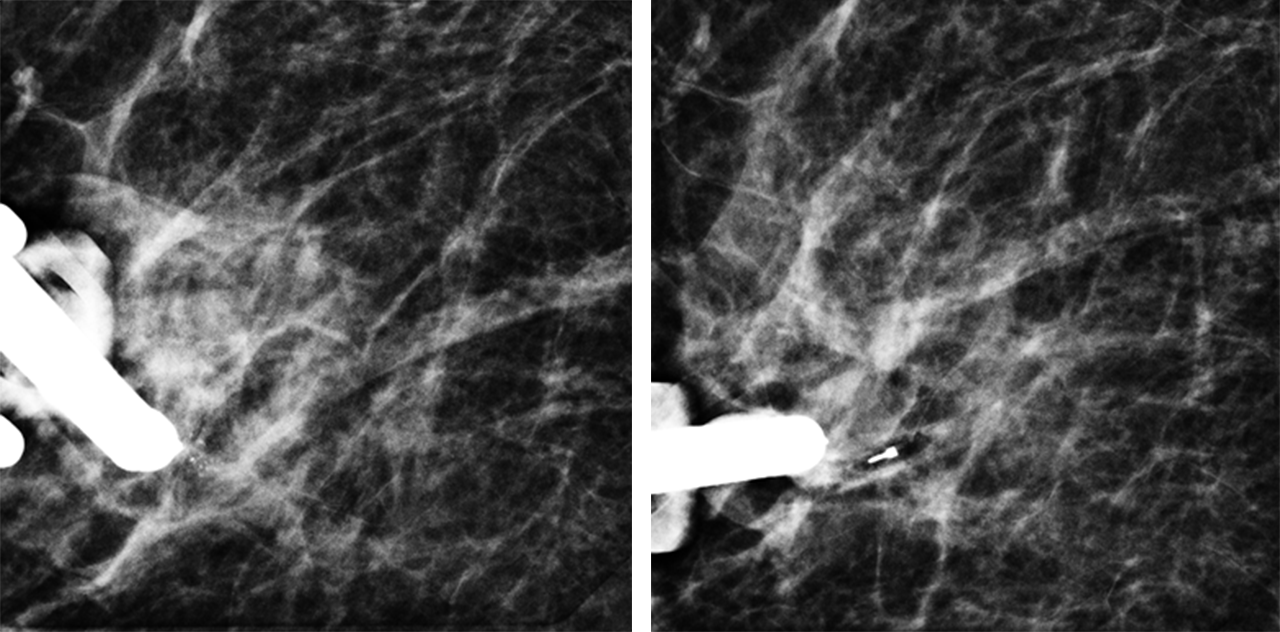

Tomosynthese-gesteuerte Vakuumbiopsie von auffälligen Verkalkungen in der rechten Brust einer 52jährigen Patientin. Im linken Bild sieht man das Verkalkungsareal. Nach Entnahme von Gewebeproben (rechtes Bild) ist das Verkalkungsareal komplett entfernt und man kann den eingelegten Markierungsclip abgrenzen.

Bei der stereotaktischen Vakuumbiopsie werden unter Röntgensicht Gewebeproben mit Hilfe einer Biopsienadel aus auffälligen Brustbereichen entnommen und anschließend durch einen Pathologen untersucht. Zumeist handelt es sich um auffällige Verkalkungen, da diese in der Regel nicht im Ultraschall oder der Kernspintomographie dargestellt werden können. Durch die feingewebliche Untersuchung der Proben kann eine bösartige Veränderung festgestellt oder ausgeschlossen werden. Der Eingriff dauert meist etwa eine Stunde und wird ambulant mit örtlicher Betäubung durchgeführt.

Hierfür steht in unserem Hause ein modernes Biopsiegerät zur Verfügung, an dem die Probeentnahme in Bauchlage Tomosynthese-gesteuert erfolgt.